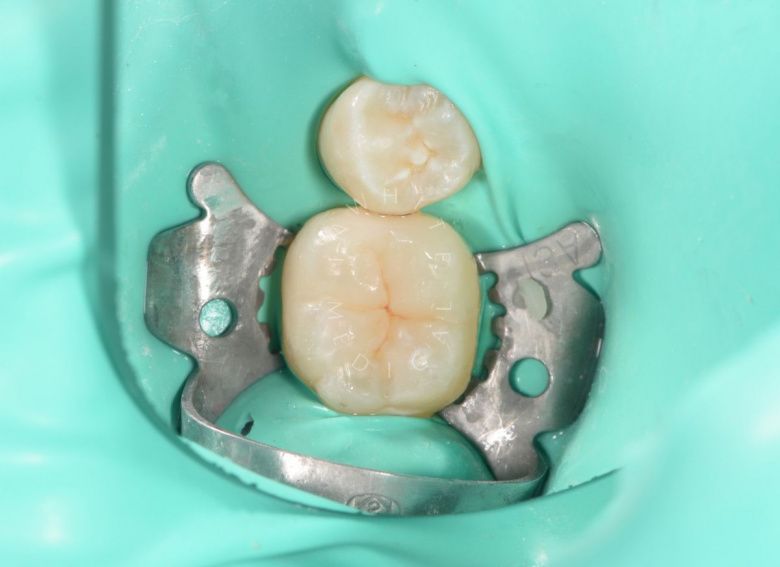

етская стоматология под наркозом Москва. Лечение молочных зубов и установка металлических коронок во сне - после процедуры